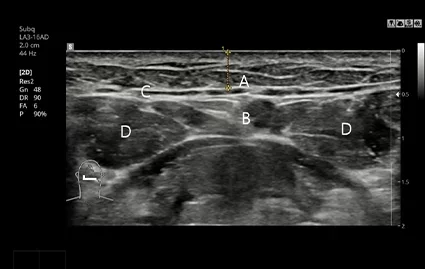

Chụp CT và siêu âm trước phẫu thuật

Thông qua chụp CT và siêu âm, bác sĩ sẽ phân tích chính xác vị trí và kích thước tuyến nước bọt,và nếu cần, tiến hành phẫu thuật loại bỏ tuyến nước bọt phù hợp theo thiết kế cá nhân hóa.